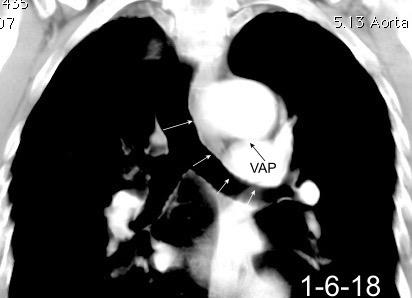

Hodgkin clásico de esclerosis nodular.

Adenopatías región cervical y mamaria interna, prevasculares y VAP. Doble contorno aórtico.